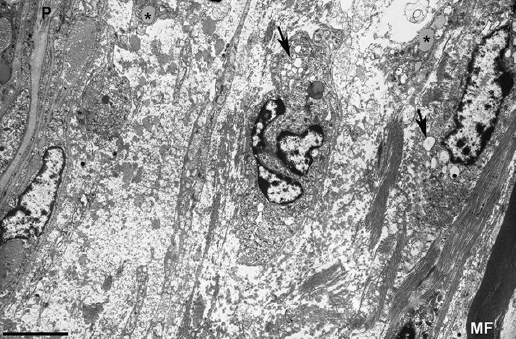

Figure 3. Electron micrograph of a subperineurial area of the fifth lumbar nerve (same the patient illustrated in Fig. 2) showing extensive edema on a ground substance of amorphous material, most likely proteoglycans, with sparse bundles of collagen fibrils. Note the presence of macrophages containing lipid droplets (asterisks) and numerous electron-lucent endocytic vesicles (arrows) and lysosomes. The edematous area is empty of myelinated fibers, the only one observed (MF) being separated about 20 mm from the inner perineurial layer; P indicates perineurium (Bar, 3 mm). Taken from Gallardo et al.14.

In a clinical-pathological paper encompassing 19 fatal GBS patients, five of whom having died within 9 days after onset (cases 1-5), Asbury et al.15 stated that “The common pathological denominator in all cases was an inflammatory demyelinative neuritis marked by focal, perivascular, and lymphocytic infiltrate, affecting at any level of the PNS […]. All levels of the PNS were vulnerable to attack, including the anterior and posterior roots, ganglia, proximal and distal nerve trunks and terminal twigs, cranial nerves, and sympathetic chains and ganglia […]. Varying amounts of Wallerian degeneration were also present, depending on the intensity and destructiveness of lesions.” Although this is the case in advanced stages of the disease16, it is worth noting that in two of their early cases (Nos 2 and 3) with pure motor signs, lesions predominantly affected the ventral roots, with more distant nerve trunks presenting minimal involvement. The authors suggested that, on the basis of the pathological features, GBS and EAN are a cell-mediated immunologic disorder, in which the PNS, particularly myelin, is attacked by specifically-sensitized lymphocytes, but stating “The question of edema is of some importance because it is not a prominent feature of the nerve and root lesions of EAN, and its alleged presence in idiopathic polyneuritis might be taken as evidence against accepting EAN as a valid model idiopathic polyneuritis. That no edema was observed in our series strengthens rather than weakens the homology between EAN and idiopathic polyneuritis. It may be that our histological criteria for accepting the presence of edema differ from those of others.” After this influential paper, the pathogenic role of inflammatory edema in very early GBS was overlooked for decades. However, the presence of endoneurial edema was demonstrated in later pathological studies17,18. Intriguingly, it has been established that edema may be a marker of disease in inflammatory neuropathies of recent onset19.